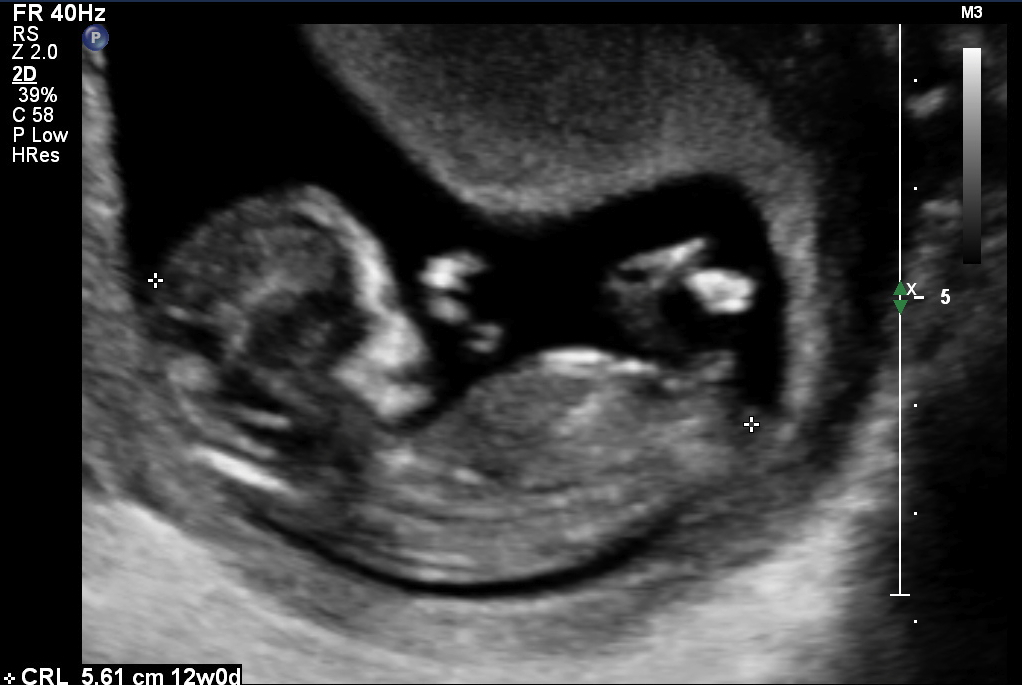

Gender guesses based on nub OR skull (up to you)

Love to hear from as many of you as possible. I find out the sex in three days so will surely pop back here and update you once i know so you know your success rate :D Attachment 15545